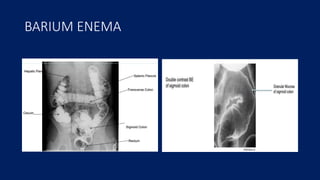

BARIUM ENEMA

Film from a barium enema examination

postinflammatory polyposis in a shortened sigmoid and descending colon in a patient with

active ulcerative colitis.